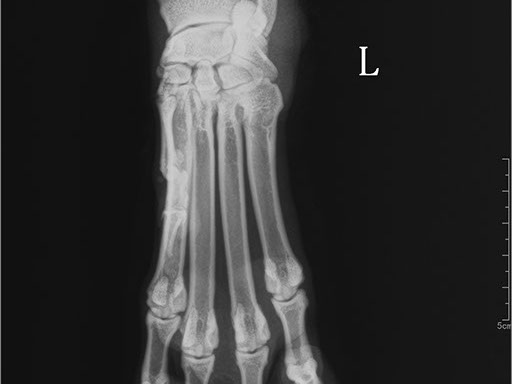

Коллиматорный прицел формирует пучок рентгеновского излучения на участок исследования. Проходя через ткани тела, излучение попадает на плоскопанельный цифровой детектор, который, в свою очередь, передает сигналы на компьютер.

В считанные секунды полученные данные обрабатываются компьютером посредством установленной на него программы визуализации, и сформированное клиническое изображение выводится на монитор лаборанта.

Клинические изображения (снимки) можно напечатать на принтере, сохранить в архиве или отправить по сети коллегам для оперативного консилиума.

Цифровая рентгеновская установка ASR-6150C поставляется с мобильным столом пациента и комплектом рентгенопрозрачных анатомических ложементов всех размеров, видов и пород домашних животных.